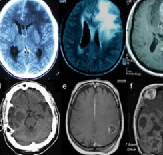

脑胶质瘤

脑胶质瘤是恶性肿瘤吗?

脑胶质瘤是恶性肿瘤吗?胶质瘤根据起源细胞系分为不同的亚型。胶质瘤包括星形细胞瘤,胶质母细胞瘤,少突胶质细胞瘤,室管膜瘤和其他组织学亚型...